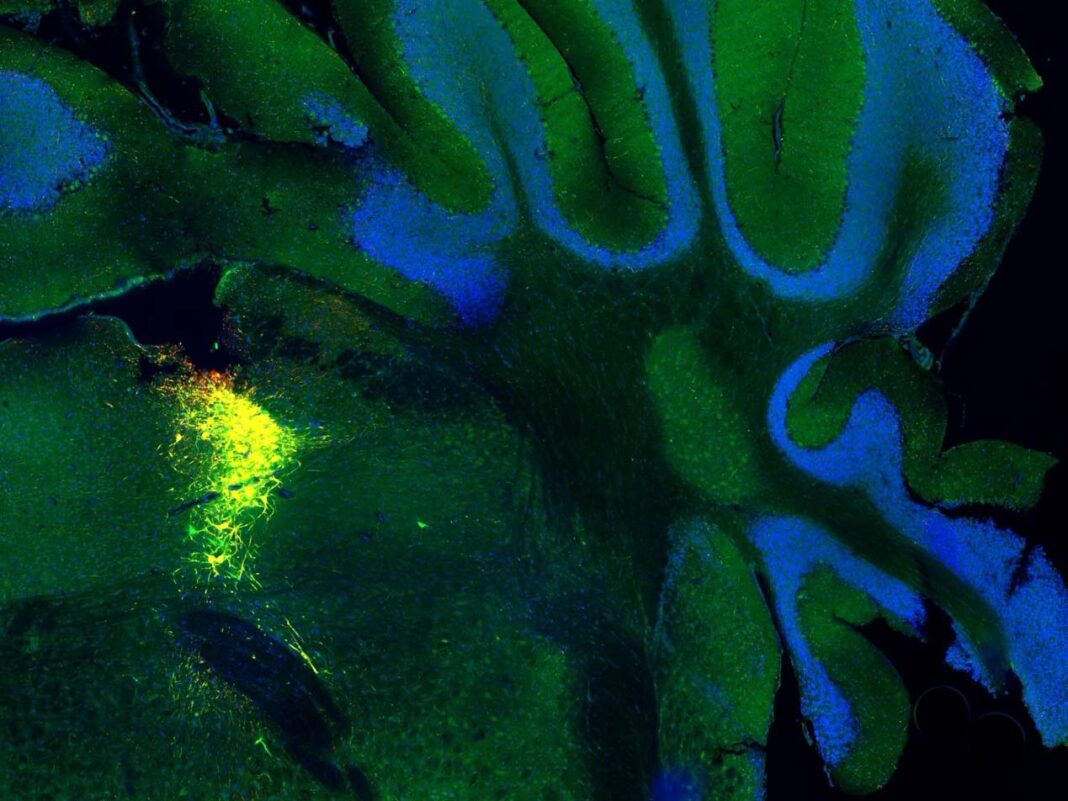

Nous avons utilisé une technique appelée « optogénétique », qui utilise des impulsions lumineuses pour activer sélectivement le locus coeruleus chez la souris tout en scannant leur cerveau par IRM.

Chaque fois que nous activions cette région, elle déclenchait le même motif d’activité cérébrale en forme d’onde, montrant qu’il s’agit d’un mécanisme fiable et contrôlable.